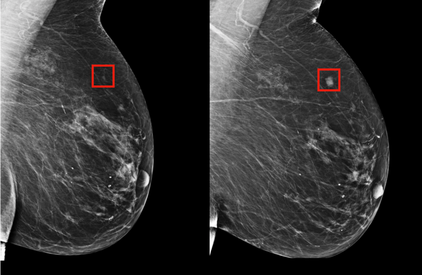

KINGSTON, Jamaica. Thursday, May 8, 2025: An artificial intelligence (AI) enhanced breast health tool is set to be introduced to Jamaica as the Ministry of Health and Wellness prioritizes breast cancer prevention and early detection efforts.

Designed for use in community settings, the radiation-free technology enables quick, non-invasive breast assessments, providing real-time decision support and helping healthcare workers detect those who need additional diagnostic evaluation.

Consultant Haematologist/Oncologist at the UHWI, Dr. Gilian Wharfe emphasised that the tool will be a gamechanger that encourages early screening. Its implementation, she says, is designed to help identify problems in early stages, when treatments are most effective. “It’s an adjunct to screening and we can then reach patients where they are, reach them in the communities, identify any abnormalities, send them on to screening and enhance their care. We’re looking for earlier diagnosis and therefore better outcomes for our patients,” Dr. Wharfe said.